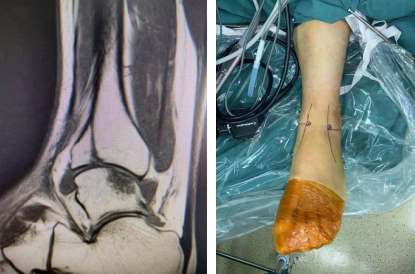

术中骨折分离移位(左图) ,术中骨折复位断端(右图)

术中韧带修复